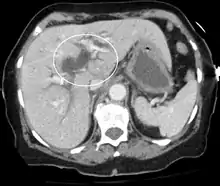

Imaging

Medical imaging such as ultrasound, CT scan, and HIDA scan are useful for detecting bile-duct blockage.[40]